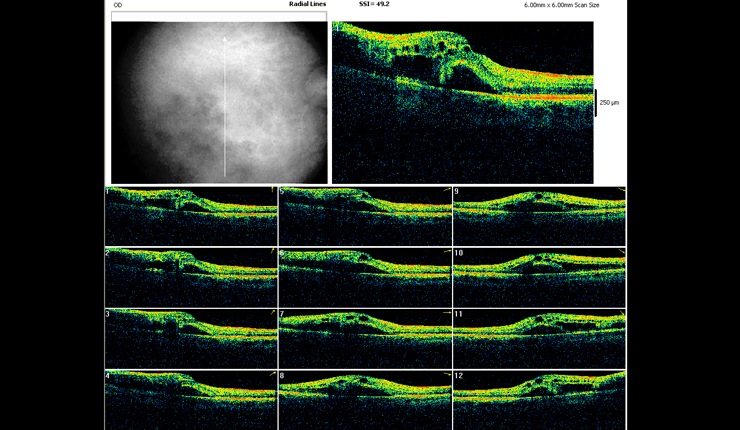

OCT radial scan display showing arcade pattern of fluid associated with branch retinal vein occlusion.